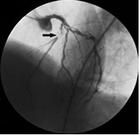

冠脈造影

冠狀動脈造影應該說是非常常規的手術,在西方國家門診做,在中國要住一、兩天院,從手上動脈插一根血管,然後打藥,看什麼地方狹窄了,狹窄部位、狹窄程度有多重,狹窄性質多長,是符合的還是單純狹窄,知道這些以後,我們才能決定這個病人用什麼治療方式比較合適,通過冠狀動脈造影之後才能告訴我們什麼信息,給病人最好指導,我們說冠狀動脈造影是做一個金指標,如果沒有它我們不可能給患者一個正確的諮詢服務。冠心病是中老年人最常見的心臟病之一,其病因由於血脂代謝異常,膽固醇和甘油三酯等逐漸沉積於血管壁上形成動脈粥樣硬化斑塊,導致心臟冠狀動脈管腔變窄,引起心臟缺血。可表現為心絞痛、心肌梗塞、心力衰竭和心源性猝死等。

冠狀動脈造影是診斷冠心病最準確的方法,醫學界稱其為“金標準”。檢查方法是通過外周動脈血管送入直徑為2毫米的造影導管至冠狀動脈造影開口,注入少量造影劑,使冠狀動脈顯影,可準確顯示血管情況。它的檢查創傷輕微,檢查一般僅需10~20分鐘,根據血管情況選擇進一步治療方案。這跟從病人在X線的幫助下,一直進入心臟的冠狀動脈,通過造影劑對左右兩冠狀動脈進行造影檢查,即可清晰分辯冠狀動脈及其分支有無狹窄,狹窄的部位及程度,以及側支循環與左心室的功能情況。

冠狀動脈造影是診斷冠心病的一種有效方法。將導管經大腿股動脈或其它周圍動脈插入,送至升主動脈,然後探尋左或右冠狀動脈口插入,注入造影劑,使冠狀動脈顯影。這樣能較明確地揭示冠狀動脈的解剖畸形及其阻塞性病變的位置、程度與範圍。

雖然心電圖等其它檢查亦可診斷冠心病,但有時並不準確,最準確的診斷冠心病的方法是冠狀動脈造影。冠狀動脈造影是目前唯一能直接觀察冠狀動脈形態的論斷方法,醫學界號稱其為“金標準”。